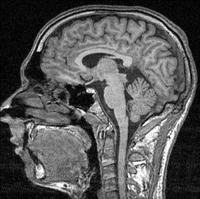

Now that we have the ability to see inside the brain without opening anyone's skull, we'll be able to map and define brain activity and peg it to behavior and feelings. Right? Well, maybe not, or maybe not just yet. It seems the workings of our brains are rather too complex and diverse across individuals to really say for certain what a brain scan says about a person. But Nobel prize winner Eric Kandel and researcher Cynthia Fu tell us about groundbreaking work in the field of depression that just may help us toward better diagnosis and treatment.

I liked this segment very much but you said fMRI can show blood flow because blood contains iron. That's a good one-sentence summary; however, fMRI imaging depends on the difference in magnetic properties depending on whether the blood's iron-bearing hemoglobin is oxygenated. When brain cells are more active, they absorb more oxygen from the blood resulting in the Blood-Oxygen-Level Dependent (BOLD) response observed with MRI equipment. For more, see http://en.wikipedia.org/wiki/Fmri.